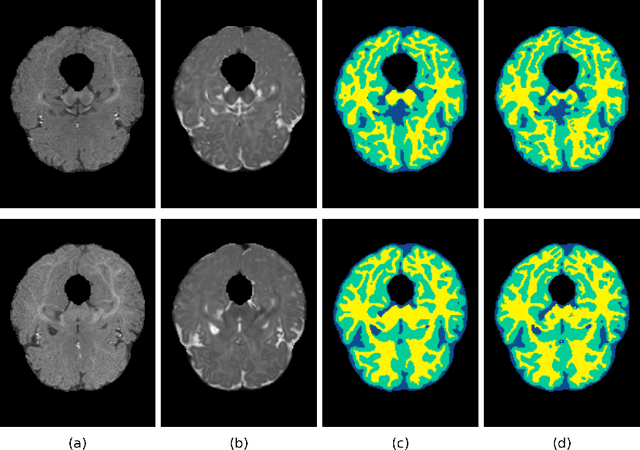

Abstract:To better understand early brain growth patterns in health and disorder, it is critical to accurately segment infant brain magnetic resonance (MR) images into white matter (WM), gray matter (GM), and cerebrospinal fluid (CSF). Deep learning-based methods have achieved state-of-the-art performance; however, one of major limitations is that the learning-based methods may suffer from the multi-site issue, that is, the models trained on a dataset from one site may not be applicable to the datasets acquired from other sites with different imaging protocols/scanners. To promote methodological development in the community, iSeg-2019 challenge (http://iseg2019.web.unc.edu) provides a set of 6-month infant subjects from multiple sites with different protocols/scanners for the participating methods. Training/validation subjects are from UNC (MAP) and testing subjects are from UNC/UMN (BCP), Stanford University, and Emory University. By the time of writing, there are 30 automatic segmentation methods participating in iSeg-2019. We review the 8 top-ranked teams by detailing their pipelines/implementations, presenting experimental results and evaluating performance in terms of the whole brain, regions of interest, and gyral landmark curves. We also discuss their limitations and possible future directions for the multi-site issue. We hope that the multi-site dataset in iSeg-2019 and this review article will attract more researchers on the multi-site issue.

Abstract:In the isointense stage, the accurate volumetric image segmentation is a challenging task due to the low contrast between tissues. In this paper, we propose a novel very deep network architecture based on a densely convolutional network for volumetric brain segmentation. The proposed network architecture provides a dense connection between layers that aims to improve the information flow in the network. By concatenating features map of fine and coarse dense blocks, it allows capturing multi-scale contextual information. Experimental results demonstrate significant advantages of the proposed method over existing methods, in terms of both segmentation accuracy and parameter efficiency in MICCAI grand challenge on 6-month infant brain MRI segmentation.